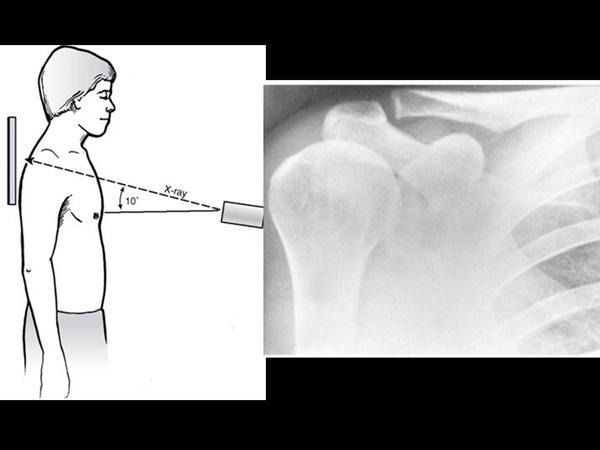

What x-ray is the money view for AC joints?

Zanca view